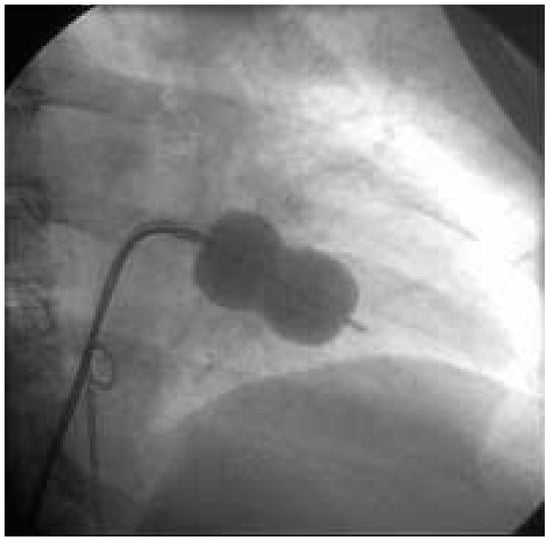

Sténose Mitrale et Valvuloplastie Mitrale Percutanée

Description du cas